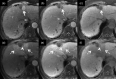

MRI is widely used in clinical practice for detecting liver diseases. Since the introduction of gadoxetic acid, MRI has become the most effective modality for the detection and characterization of focal liver lesions. According to previous meta-analyses, the area under the receiver operating characteristic curve (AUROC) was 0.97-0.99 for the diagnosis of small hepatocellular carcinoma (≥ 2 cm) by gadoxetic-acid-enhanced MRI. Moreover, the AUROC for the diagnosis of colorectal liver metastases was significantly high (0.98). Despite gadoxetic acid's drawbacks, its clinical utility outweighs them, making it the contrast agent of choice in routine liver MRIs. Moreover, clinically, liver MRI has become more prevalent for a quantitative assessment. Liver fibrosis can be evaluated using MR elastography; whereas, hepatic steatosis and iron overload can be evaluated using proton density fat fraction, with high accuracy and reproducibility. This article reviewed the usefulness of liver MRI, which can be a comprehensive imaging modality in clinical practice.